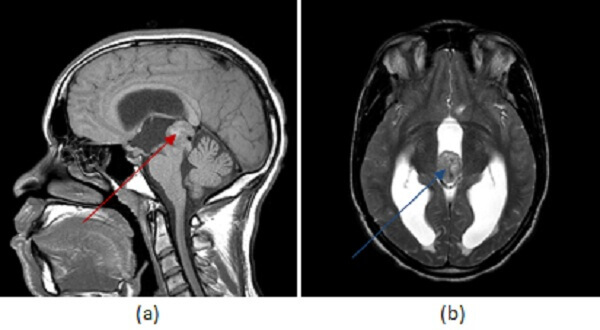

Figure 1: Pineal mass with heterogenous T1 (a, red arrow) and T2 (b, blue arrow) signal . The mass also heterogeneously enhances on post contrast T1 sequences (c, green arrow) and is associated with hydrocephalus (purple arrow).

Unlike pineal cell tumors, germinomas tend to “engulf” pineal calcifications, displacing them inwards. They are also typically associated with elevated serum markers. Germinoma’s account for about 60% of GCT’s, are associated with elevations in BHCG and occur disproportionately in young men. Situated in the midline around the third ventricle, they may involve sites other than the pineal gland, including the parasellar region and the basal ganglia. In fact, simultaneous pineal and suprasellar teratomas occur in 20% of cases. Germinomas have intense, uniform enhancement and may disseminate throughout the CSF. As a result, complete imaging of the brain and spine should be performed prior to treatment to evaluate the extent of disease. The presence of intra-tumoral cysts correlates with a worse prognosis. Treatment includes radiation and chemotherapy.

Masses in the pineal region can compress the third ventricle leading to hydrocephalus or compress the dorsal midbrain inferiorly resulting in paralysis of upward gaze and nystagmus from compression of the superior colliculus and oculomotor nucleus (Perinaud’s syndrome).